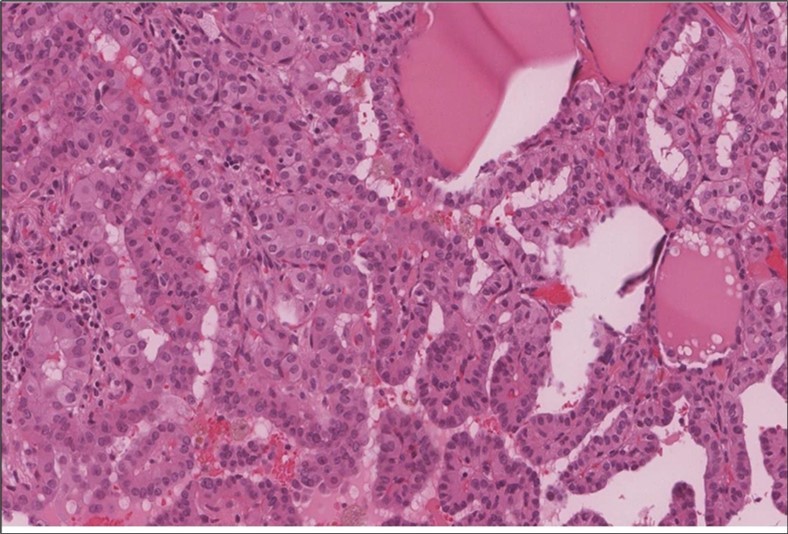

cancer, or other metastatic tumors without further testing with genetic or molecular studies 3, 7. Immunohistochemical testing plays a vital role in differentiating LMS from such similar tumors as it stains positive for vimentin and smooth muscle actin (SMA), and is variably positive for HHF35, desmin (50%-100%), and H-caldesmon 3, 6. Moreover, there were no reported cases where thyroid LMS stained positive for thyroglobulin, cytokeratin, calcitonin, chromogranin, or protein S100 3. Our patient’s left thyroid biopsy showed the characteristic microscopic features and was positive for SMA, desmin, caldesmon, P63 with patchy EMA (Figure 1, Figure 2, Figure 3, Figure 4) as well as her liver biopsy (Figure 5, Figure 6, Figure 7); whereas her right thyroid showed clear papillary thyroid cancer cell features (Figure 8, Figure 9).

Figure 8.Right thyroid Right thyroid lobe shows foci of papillary thyroid carcinoma. (H&E, x4)).

Figure 9.Right thyroid Higher power showing the characteristic nuclear features of papillary thyroid cancer nuclear enlargement, elongation and overlapping, chromatin clearing, margination and glassy nuclei. (H&E, ×200).